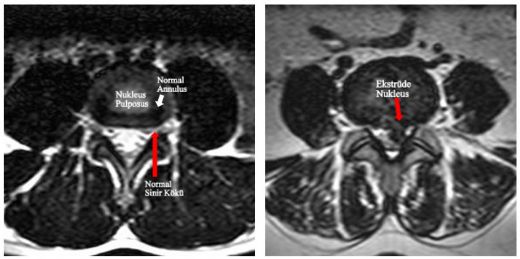

Bel fıtığı yırtılması tanısı, genellikle fiziksel muayene ve görüntüleme yöntemleri ile konur. Doktor, hastanın belirtilerini değerlendirir ve aşağıdaki testleri isteyebilir:

• MR (Manyetik Rezonans) Taraması: Disklerin durumu ve sinirlerin etkilenip etkilenmediğini değerlendirmek için en etkili yöntemdir.